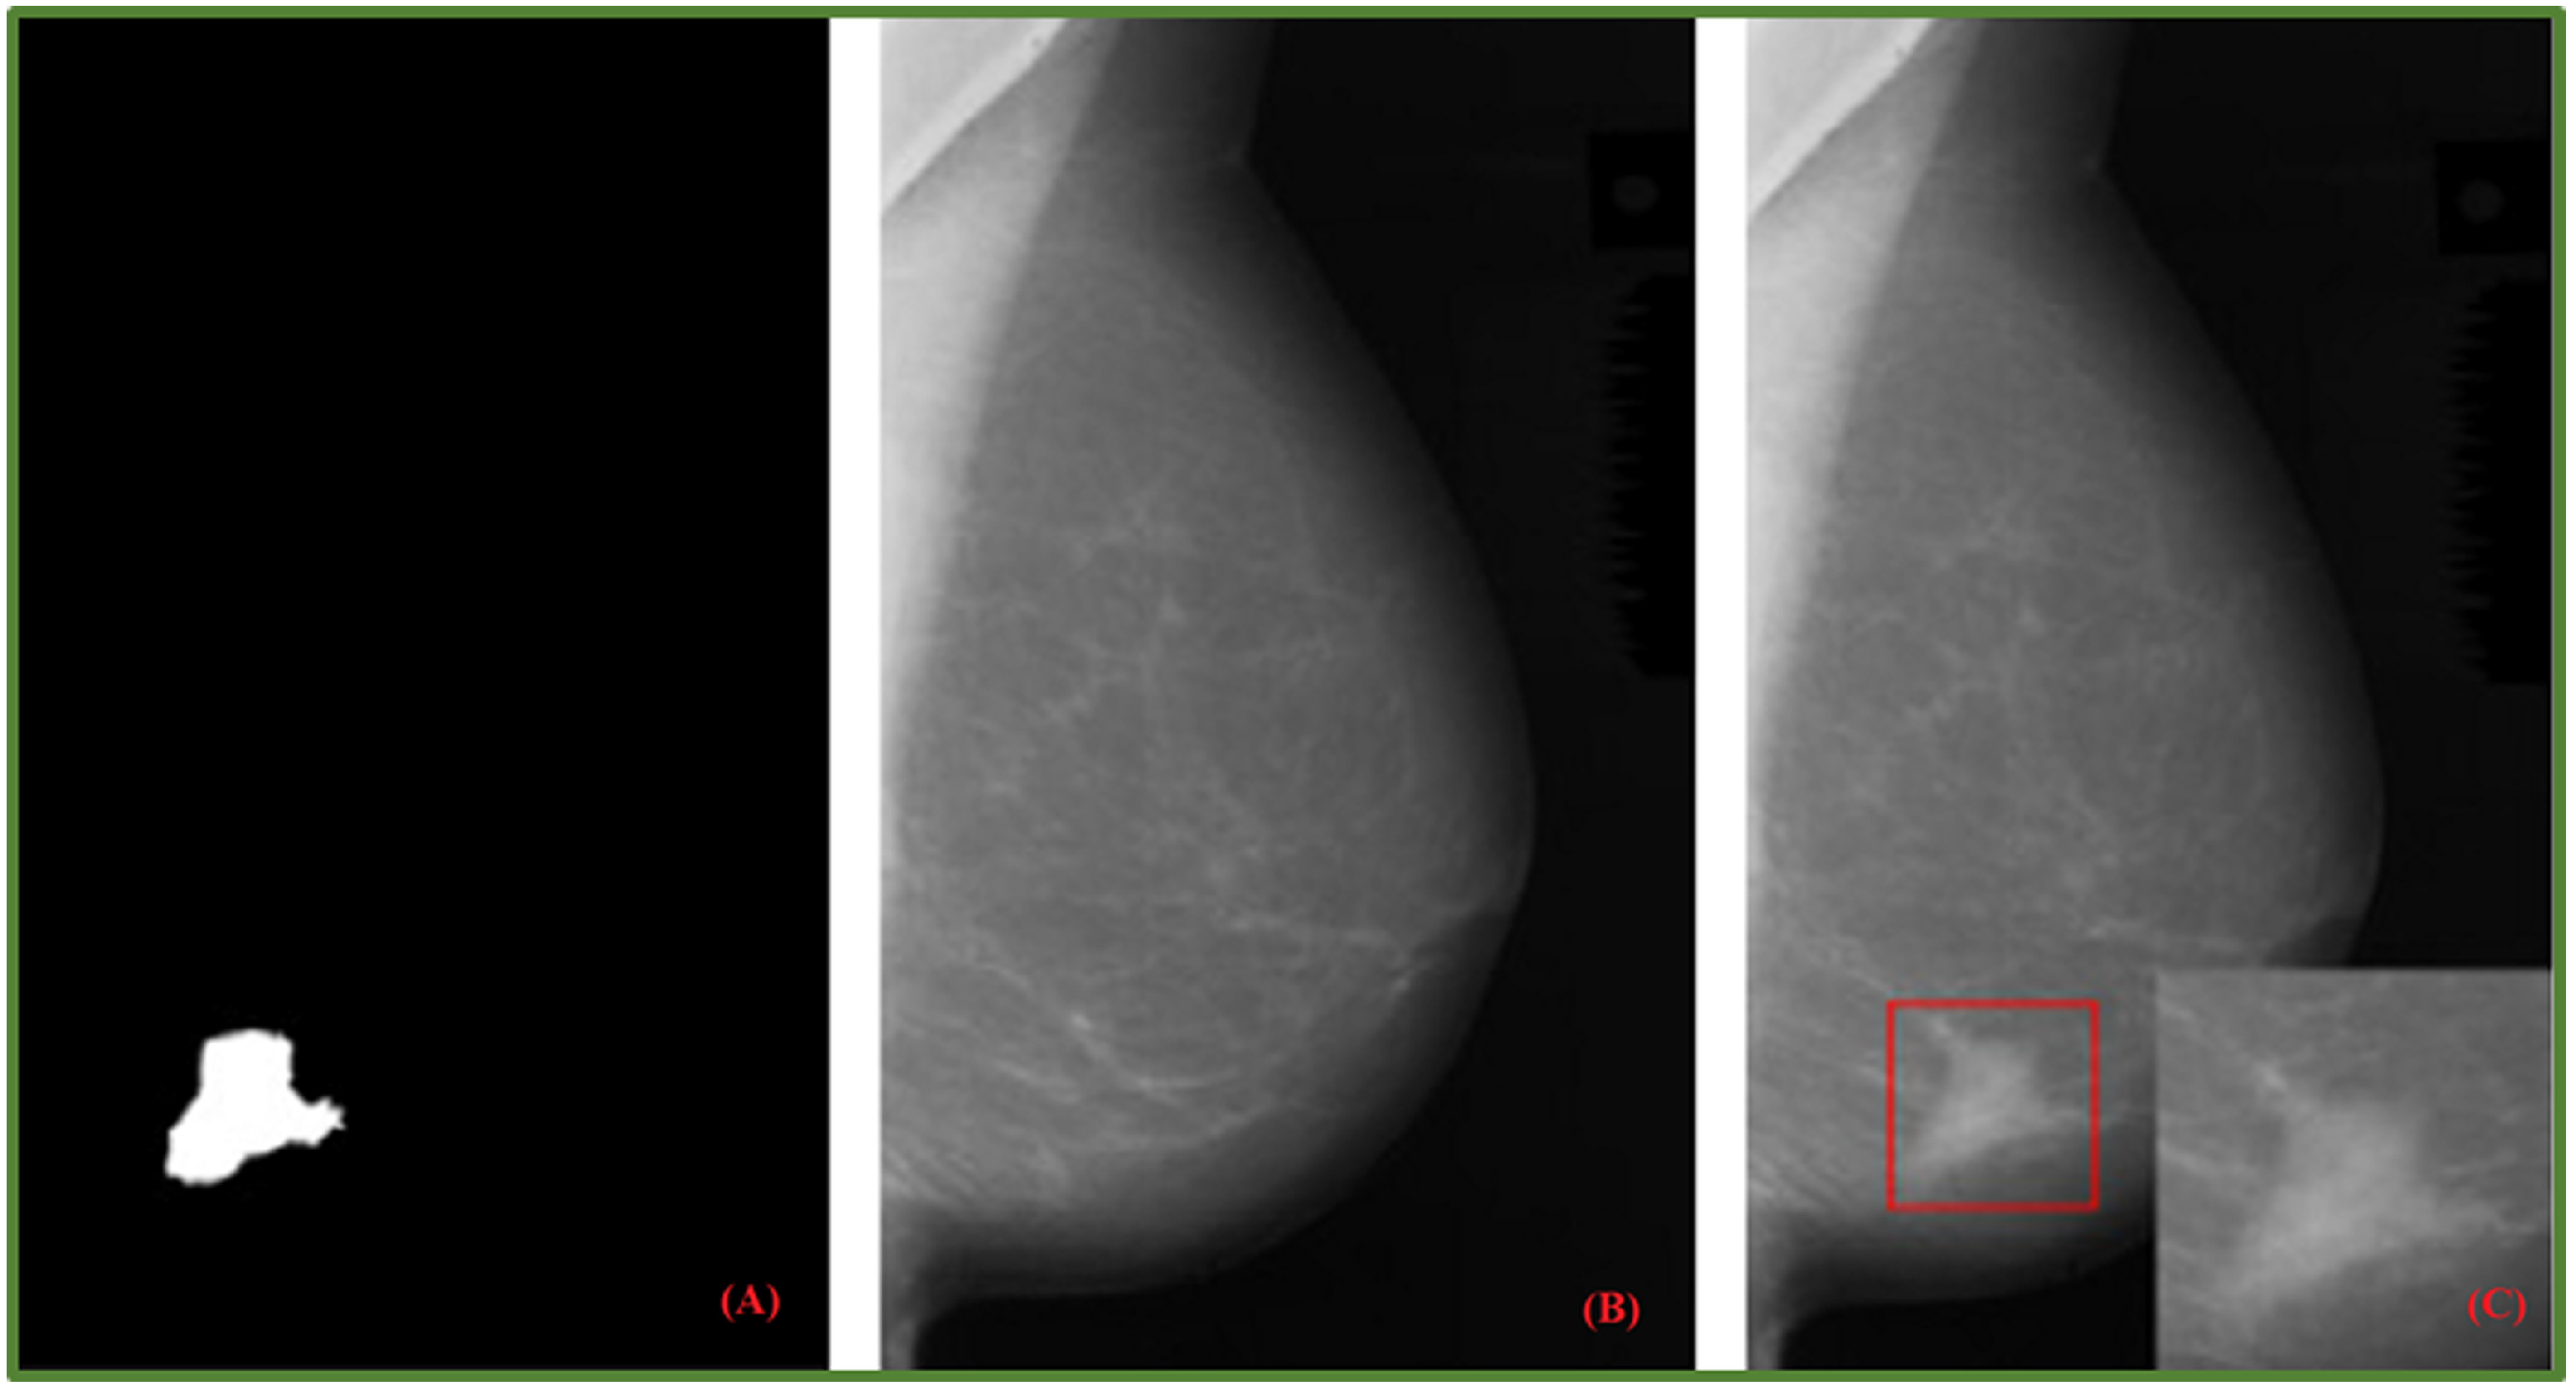

- Costa, A.C.; Oliveira, H.C.; Vieira, M.A. Data augmentation: Effect in deep convolutional neural network for the detection of architectural distortion in digital mammography. In Proceedings of the Brazilian Congress on Medical Physics, Santos, Brazil, 21–24 August 2019. [Google Scholar]

- Cha, K.H.; Petrick, N.A.; Pezeshk, A.X.; Graff, C.G.; Sharma, D.; Badal, A.; Sahiner, B. Evaluation of data augmentation via synthetic images for improved breast mass detection on mammograms using deep learning. J. Med. Imaging 2019, 7, 012703. [Google Scholar] [CrossRef] [PubMed]

- Zeiser, F.A.; da Costa, C.A.; Zonta, T.; Marques, N.; Roehe, A.V.; Moreno, M.; da Rosa Righi, R. Segmentation of masses on mammograms using data augmentation and deep learning. J. Digit. Imaging 2020, 33, 858–868. [Google Scholar] [CrossRef] [PubMed]